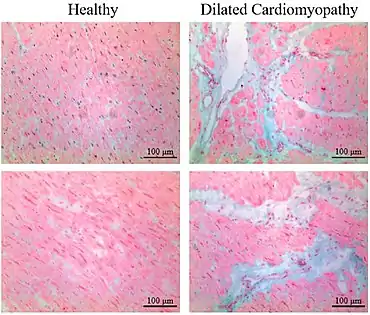

Differential diagnoses for myocardial fibrosis:

- Interstitial fibrosis, which is nonspecific, having been described in congestive heart failure, hypertension, and normal aging.[25]

- Subepicardial fibrosis, which is associated with non-infarction diagnoses such as myocarditis[26] and non-ischemic cardiomyopathy.[27]

Healthy myocardium versus interstitial fibrosis in dilated cardiomyopathy. Alcian blue stain.

Healthy myocardium versus interstitial fibrosis in dilated cardiomyopathy. Alcian blue stain. Subepicardial fibrosis (epicardium at top)